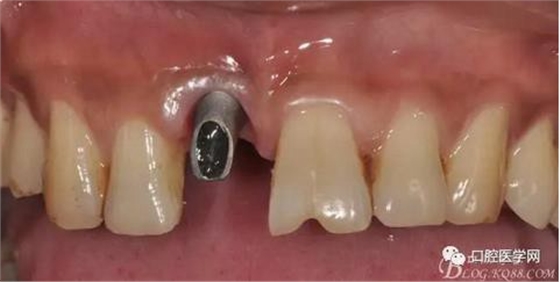

圖9 三個月后袖口形成正位照

圖10 三個月后袖口形成頜面照